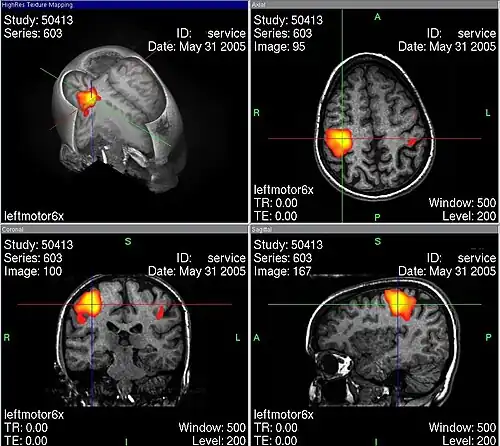

Übersicht der verschiedenen Beobachtungsebenen einer fMRT-Aufnahme nach linksseitigem „Finger-Tapping“. Die farbig dargestellten Bereiche symbolisieren einen erhöhten Stoffwechsel und somit eine Hirnaktivität. Je weiter die Farbe ins Gelbliche abweicht, desto wahrscheinlicher ist Aktivität. Die Darstellung der Hirnaktivität erfolgt über die BOLD-Antwort der Hirnregionen (siehe Haupttext).

Durch fMRT-Aufnahmen ist es möglich, Durchblutungsänderungen von Hirnarealen sichtbar zu machen, die auf Stoffwechselvorgänge zurückgeführt werden, welche wiederum mit neuronaler Aktivität in Zusammenhang stehen. Hierbei macht man sich die unterschiedlichen magnetischen Eigenschaften von oxygeniertem und desoxygeniertem Blut zunutze (BOLD-Kontrast). Bei der Aktivierung von Kortexarealen kommt es zu einer Steigerung des Stoffwechsels, wodurch das aktivierte Areal mit einer überproportionalen Erhöhung des Blutflusses reagiert (sog. neurovaskuläre Kopplung). Dadurch erhöht sich die Konzentration von oxygeniertem (diamagnetischem) relativ zu desoxygeniertem (paramagnetischem) Hämoglobin. Über den intermolekularen Elektronendipol-Kerndipol-Relaxationsmechanismus bewirkt diese Konzentrationsänderung eine Veränderung der effektiven transversalen Relaxationszeit der beobachteten Wasserstoff-Kernspins und führt damit zu einer Signaländerung in der MRT. Um so Rückschlüsse auf den Ort einer neuronalen Aktivität zu ziehen, wird das Magnetresonanz-Signal des Gewebes zu zwei Zeitpunkten verglichen – z. B. im stimulierten oder Experimentalzustand einerseits sowie im Ruhe- oder Kontrollzustand andererseits. Die Aufnahmen können durch statistische Testverfahren miteinander verglichen und die statistisch signifikanten Unterschiede (die den stimulierten Arealen entsprechen) räumlich zugeordnet und dargestellt werden.

Bei einer Untersuchung des Gehirns zu Versuchszwecken kann dem Probanden im dritten Teilscan zum Beispiel ein wiederholter Reiz präsentiert werden. Häufig wird der Reiz mit einer Aufgabe für den Probanden verknüpft, etwa der Aufforderung, bei jedem gezeigten Objekt X eine Taste zu drücken. Den meisten Versuchen gemein ist die häufige Wiederholung der Aufgabe. So kann dann durch statistische Verfahren ein Vergleich aufgezeichneter Daten aus der Reizphase mit denen aus der Ruhephase stattfinden. Der hieraus berechnete Unterschied wird dann in Falschfarben auf den zuvor durchgeführten anatomischen MR-Scan projiziert.